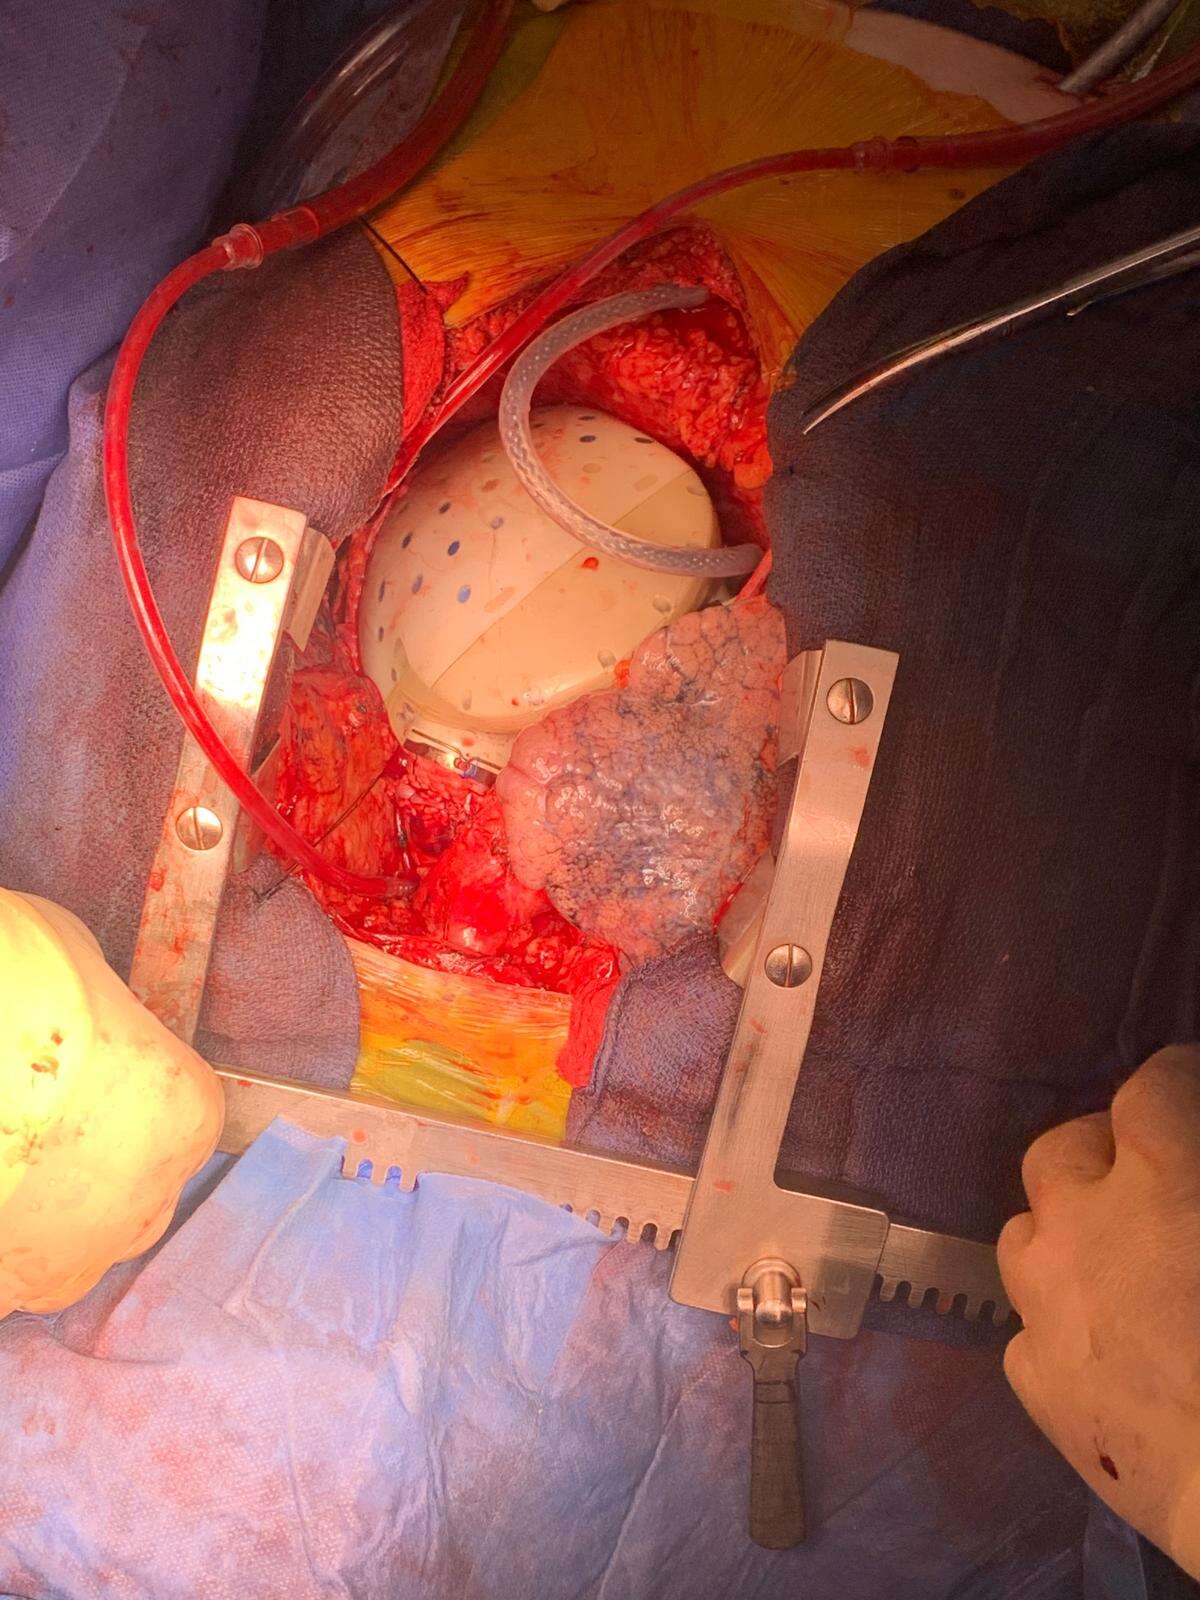

The patient's diseased heart was removed entirely and replaced with a unique artificial heart made of titanium, combined with animal-derived biological tissues and advanced sensors.

The complex operation took place on Sunday and lasted seven hours. It was carried out by a large team of cardiologists, heart surgeons, anesthesiologists, intensive care specialists, operating room nurses, and heart-lung machine technicians. The patient's diseased heart was completely removed and replaced with a special artificial heart made of titanium, incorporating biological tissues from animals and advanced sensors.

During the operation, the artificial heart was prepared in one operating room, with artificial valves added to the device. In a separate room, surgeons removed the patient's heart and connected him to a heart-lung machine. Once the artificial heart was ready, it was implanted and connected to the patient's main blood vessels.

Initially, the patient was supported by an ECMO machine, which performs the functions of the heart and lungs. Gradually, doctors reduced the machine's output as the artificial heart took over, eventually disconnecting the patient entirely. The artificial heart began functioning on its own.

The device was developed by French company CARMAT, represented in Israel by Tzamal Medical. A heart costs 1.6 million shekels (about $430,000), and in this case was funded by Clalit, where the patient is insured.